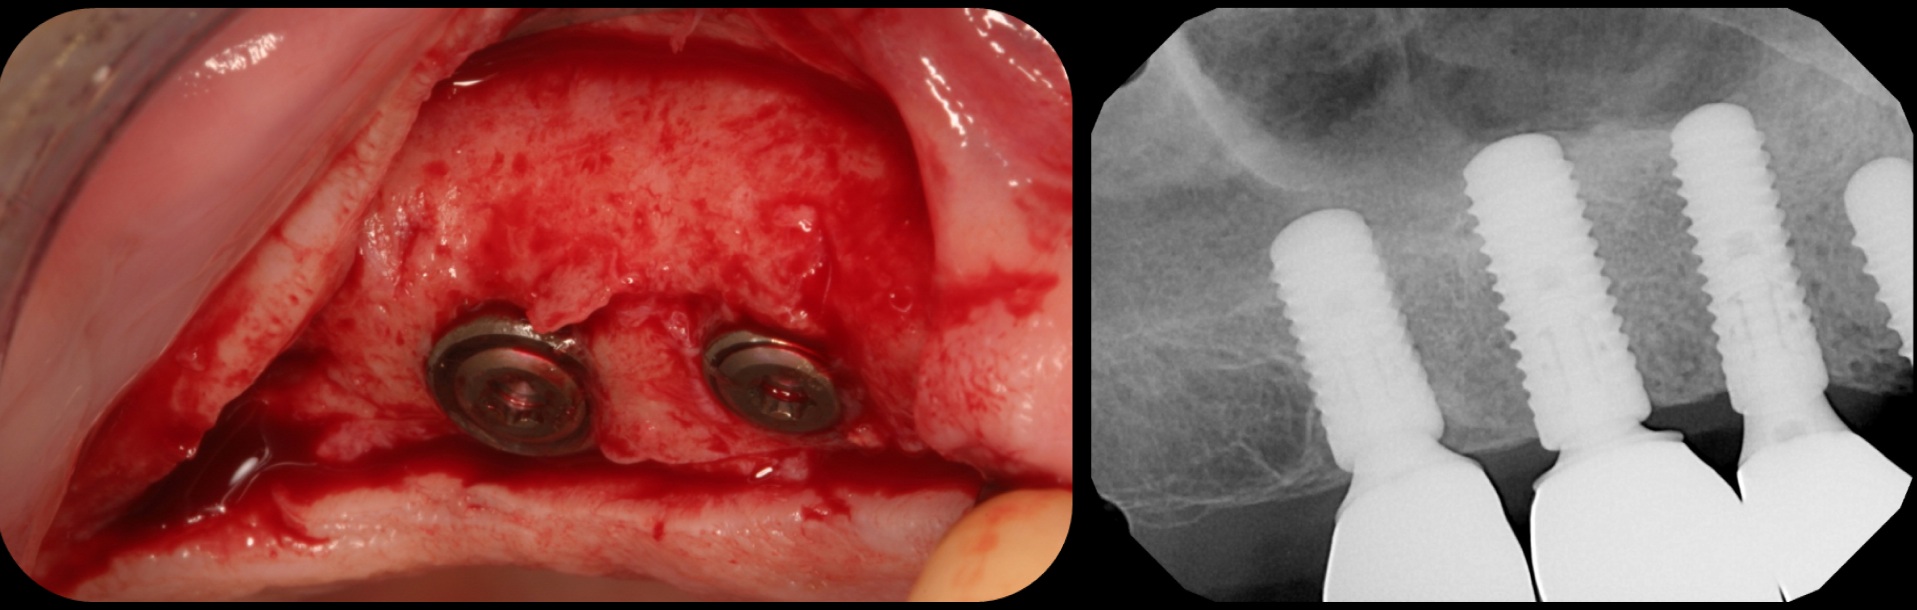

Severe periodontitis lesion.

Fig. 2

Facial bone loss and a mesial vertical defect.

Fig. 3

Then, too, are opportunities to prepare the site for regeneration by coupling therapies, applying an enamel matrix derivative, along with traditional bone grafts of demineralized freeze-dried bone allograft; potentially, gains in attachment with minimal probing depth and retained papilla may avoid the need for an implant (Figure 2 through Figure 7).